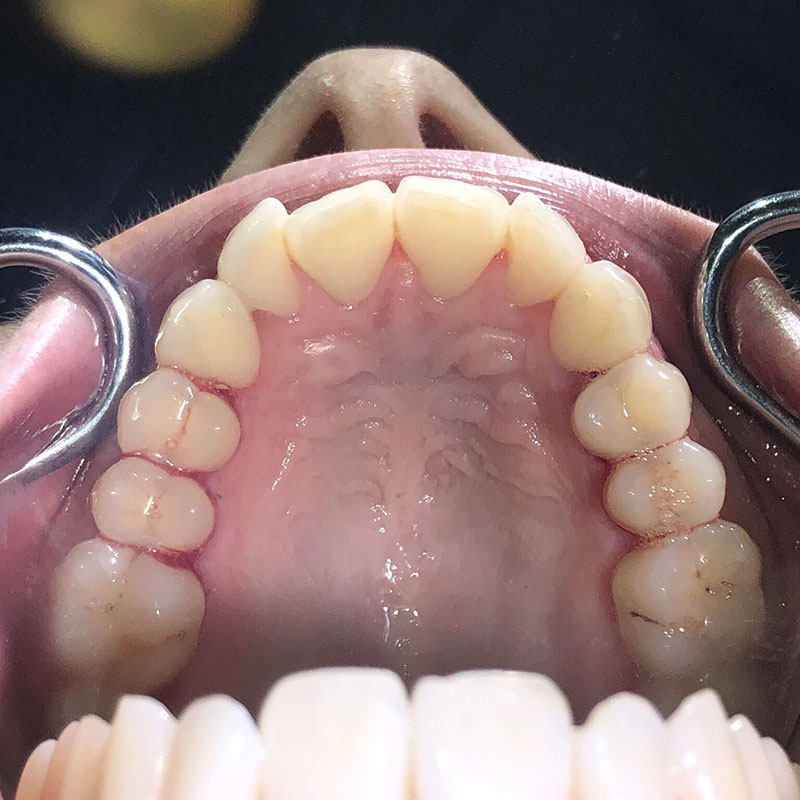

Patiente de 34 ans venue au cabinet pour une réhabilitation de son sourire suite à une récidive de son traitement d’orthodontie survenue pendant son adolescence, à cause du non-remplacement de sa contention perdue. Elle avait eu dans le passé une proposition de traitement par facettes pour réaliser l’alignement qu’elle avait refusé, ne voulant pas que l’on touche à ses dents.

À l’examen clinique, la patiente est en classe I d’Angle molaire bilatérale, indication idéale pour les traitements d’alignement simples que peuvent réaliser les omnipraticiens formés à cette thérapeutique.

Aucune autre pathologie ni problème dentaire ne furent relevés, en dehors d’un nettoyage préalable.